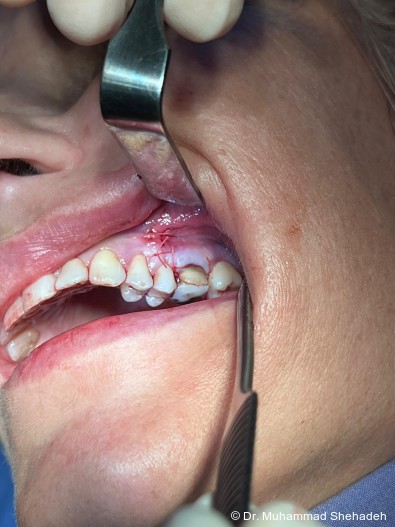

Nach ausführlicher Aufklärung wurde gemeinsam mit der Pa­tien­tin entschieden, den Zahn 26 durch eine Wurzelspitzen­resektion (WSR) zu erhalten und gleichzeitig den Fremd­­körper über den WSR-Zugang aus der Kieferhöhle in Lokal­­anäs­­thesie zu entfernen. Die operative Maßnahme erfolgte unter antibiotischer Abschirmung mit Amoxicillin/Clavulansäure.

Intraoperativ wurde ausgeprägtes entzündliches Weich­gewebe in der linken Kieferhöhle sichtbar, das vollständig entfernt wurde. Zudem konnte ein schwarz-grünlicher, bröcke­liger Fremdkörper geborgen werden, der makroskopisch dem Erscheinungsbild eines Fungusballs entsprach. Die histopathologische Untersuchung bestätigte den Verdacht: Es fanden sich multiple Myzelstrukturen, vereinbar mit einem Myze­tom (Fungusball).